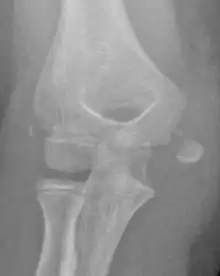

Medial Epicondyle Fracture of the Humerus

The diagnosis is confirmed with X-rays and occasionally with a CT scan.

In all injuries to the medial epicondyle, radiographs (x-rays) are imperative. Computed tomography scans are occasionally useful in evaluating the degree of fracture displacement or the involvement of the joint surface.